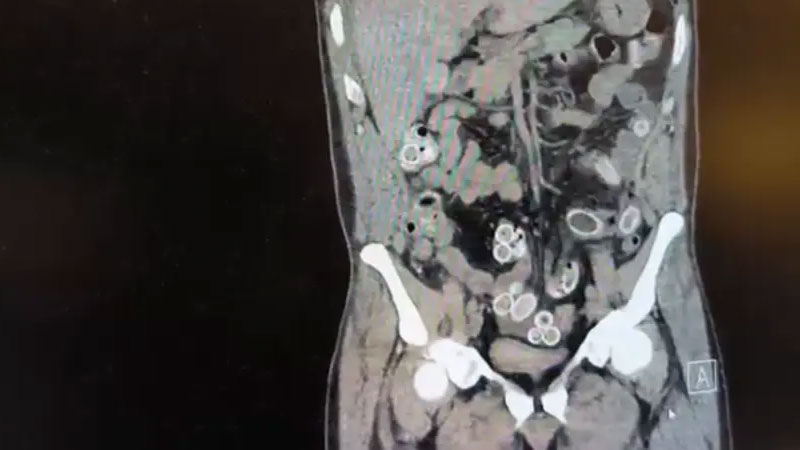

Yapılan muayenenin ardından Cüneyt G.’nin tomografisi çekildi. Şüphelinin mide ve bağırsaklarında yabancı madde tespit edilmesi üzerine hastane yetkilileri durumu polis ekiplerine bildirdi.

ESRAR KAPSÜLLERİ AMELİYATLA ÇIKARILDI

Doktorların değerlendirmesi sonrası ameliyata alınan Cüneyt Ç.’nin bağırsaklarından, toplam ağırlığı 259,7 gram olduğu öğrenilen 49 esrar macunu çıkarıldı.